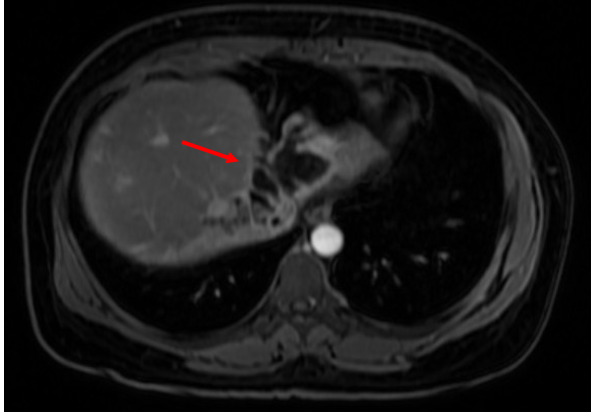

- MRI gan – mật (29/11): Hình ảnh dày đường mật gan trái kèm các đám ngấm thuốc muộn quanh đường mật gan trái (kích thước 68 x 23 mm) – theo dõi viêm mạn tính, chưa loại trừ u đường mật. Xơ gan. Giãn tĩnh mạch cửa (Hình 2).

Hình 2. Hình ảnh giãn và dày đường mật gan trái (mũi tên đỏ) và không còn thấy các nốt ngấm thuốc trên MRI sau điều trị kháng sinh

- Sinh thiết u gan, mô bệnh học: Để khẳng định có u khan hay không, bệnh nhân đã được chỉ định sinh thiết khối ở gan, kết quả là Không thấy tế bào ác tính